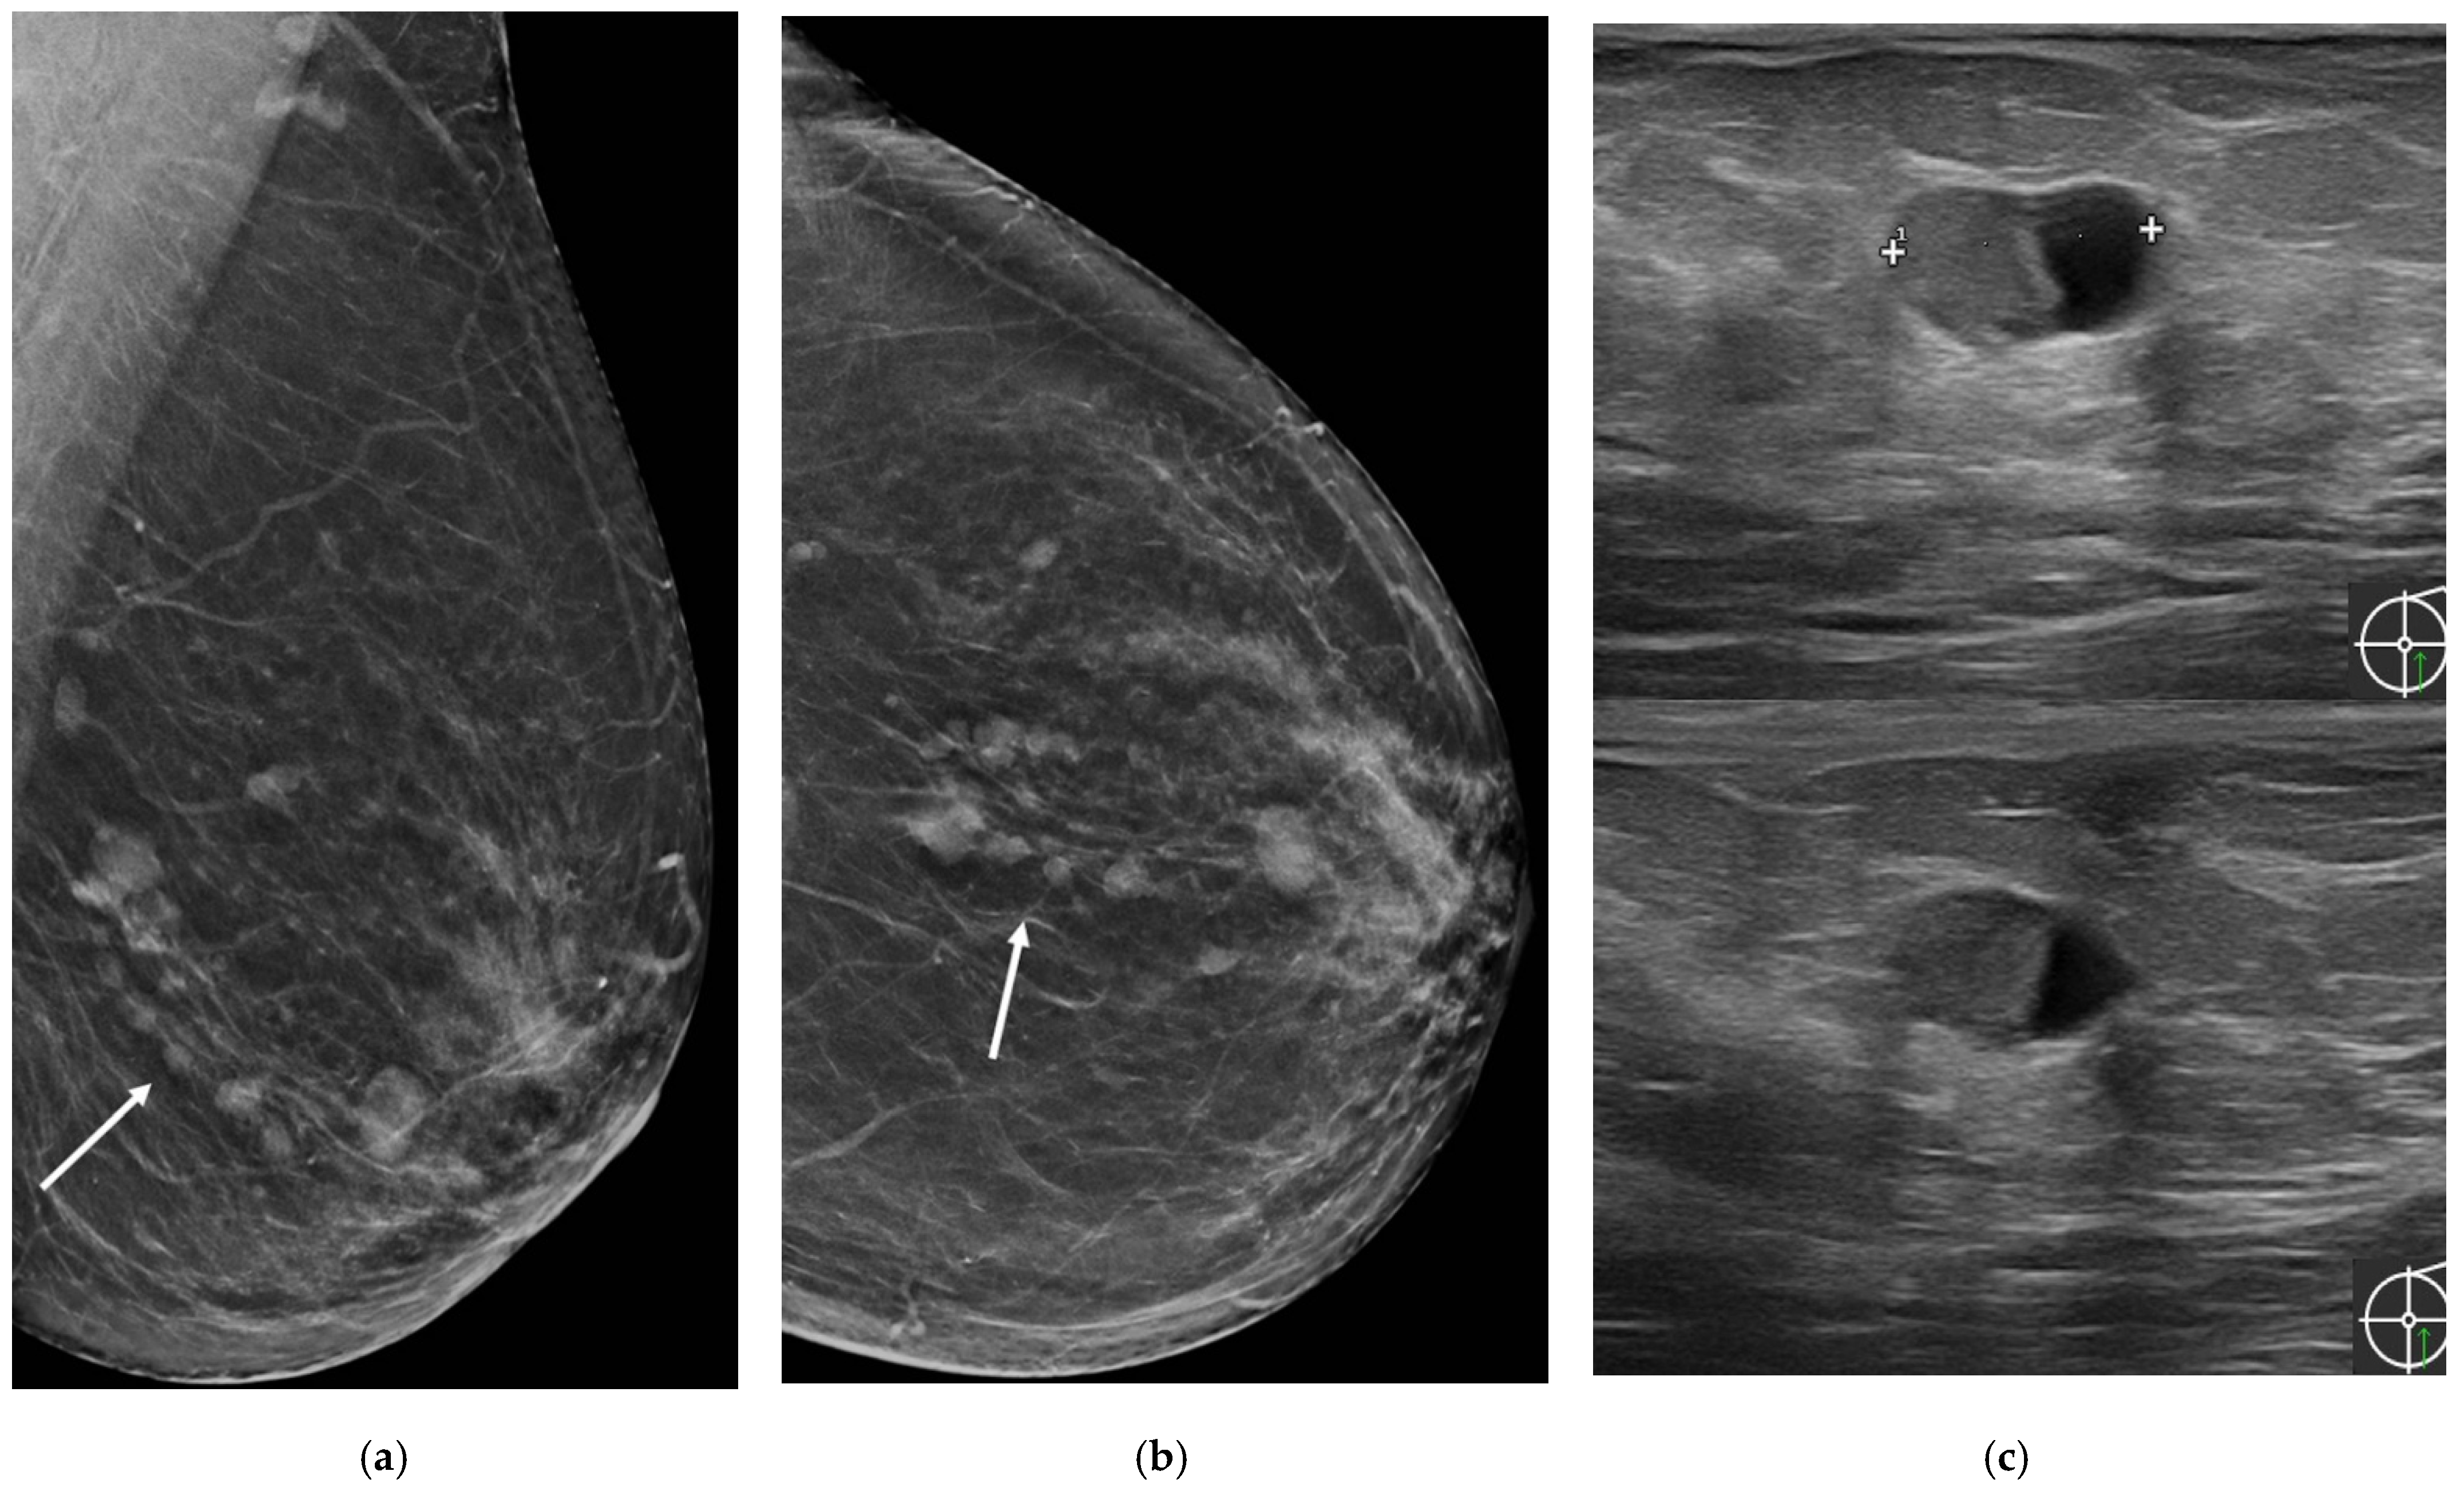

| Son 2009 [25] | Retrospective cohort, patients who underwent surgery due to papillomas of the breast and performed 3D fast low-angle shot (FLASH) dynamic breast MRI | NR | 3 | 41.7 ± 12.9 (27–51) | 2/3 palpable mass, 1/3 bloody nipple discharge | MX: 2/3 microcalcifications US: 3/3 multiple masses MRI: 1/3 multiple nodular enhancement; 1 ductal non-mass enhancement, 1 segmental non-mass enhancement | NR | NR | NR | |

| Sarica 2018 [26] | Retrospective cohort, patients with a pathologic diagnosis of papillary lesion who performed MRI and US | NR | 11 | 41.45 ± 7.7 | 1/11 palpable mass, 3/11 unilateral nipple discharge | US: 3/11 dilated duct partially/completely filled with intraluminal content; 1/11 mass with ductal relation or intracystic mass; 6/11 heterogeneous tubular nonmass-like hypoechoic area or mass related to multiple dilated ducts; 1/11 occult MRI: 3/11 dilated duct and intraductal focal mass on T2; 2/11 Dilated duct and pre-contrast high T1 signal; 2/11 mass with crescentic peripheral fluid; 3/11 mass related with dilated duct-ductal contrast enhancement; 1/11 linear-ductal contrast enhancement; 3/11 segmental contrast enhancement | NR | NR | NR | |